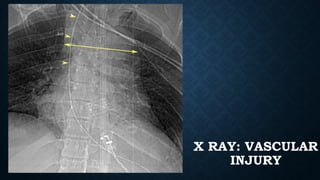

VASCULAR INJURY: SIGNS

• Signs of mediastinal hematoma

Widened mediastinum

Indistinct or abnormal aortic contour

Deviation of trachea or NGT to the right

Depression of left main bronchus

Widened paraspinal stripe

X RAY: VASCULAR

INJURY